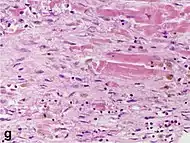

Under the microscope, myocardial infarction presents as a circumscribed area of ischemic, coagulative necrosis (cell death). On gross examination, the infarct is not identifiable within the first 12 hours.[20]

Although earlier changes can be discerned using electron microscopy, one of the earliest changes under a normal microscope are so-called wavy fibers.[21] Subsequently, the myocyte cytoplasm becomes more eosinophilic (pink) and the cells lose their transversal striations, with typical changes and eventually loss of the cell nucleus.[22] The interstitium at the margin of the infarcted area is initially infiltrated with neutrophils, then with lymphocytes and macrophages, who phagocytose ("eat") the myocyte debris. The necrotic area is surrounded and progressively invaded by granulation tissue, which will replace the infarct with a fibrous (collagenous) scar (which are typical steps in wound healing). The interstitial space (the space between cells outside of blood vessels) may be infiltrated with red blood cells.[20]

These features can be recognized in cases where the perfusion was not restored; reperfused infarcts can have other hallmarks, such as contraction band necrosis.[23]